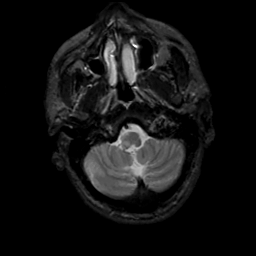

MR Study #5, March 10, 1991 -- Slice #8

[Home][Help][Clinical][Tour 1][Tour 2] Slice 8